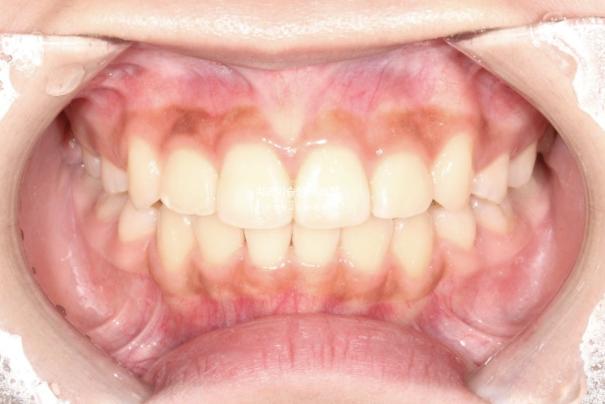

23년 10월 교정치료를 위해 온 중학생 환자입니다.

고치고 싶은 것은 돌출입

덧니도 있고 치열도 삐뚤하여 작은어금니 4개 발치가 필요한 상황입니다.

아래턱이 작은 무턱이지만, 아래턱 성장을 유도하는 성장교정을 할 시기는 지났고

돌출입만 해소가 되어도 무턱이 완화되어 보임을 설명드리고 치료에 들어갔습니다.

인비절라인을 선택하셨고 첫 세트 장치는 88개가 나왔습니다.